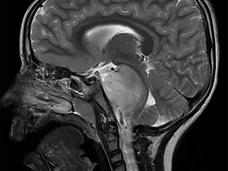

Studies Identify Potential Treatment Strategies for Pediatric DIPG Brain Tumors

Two studies have identified proteins that drive growth of diffuse intrinsic pontine glioma (DIPG) tumor cells. Blocking these targets with investigational drugs slowed tumor growth in animal models.